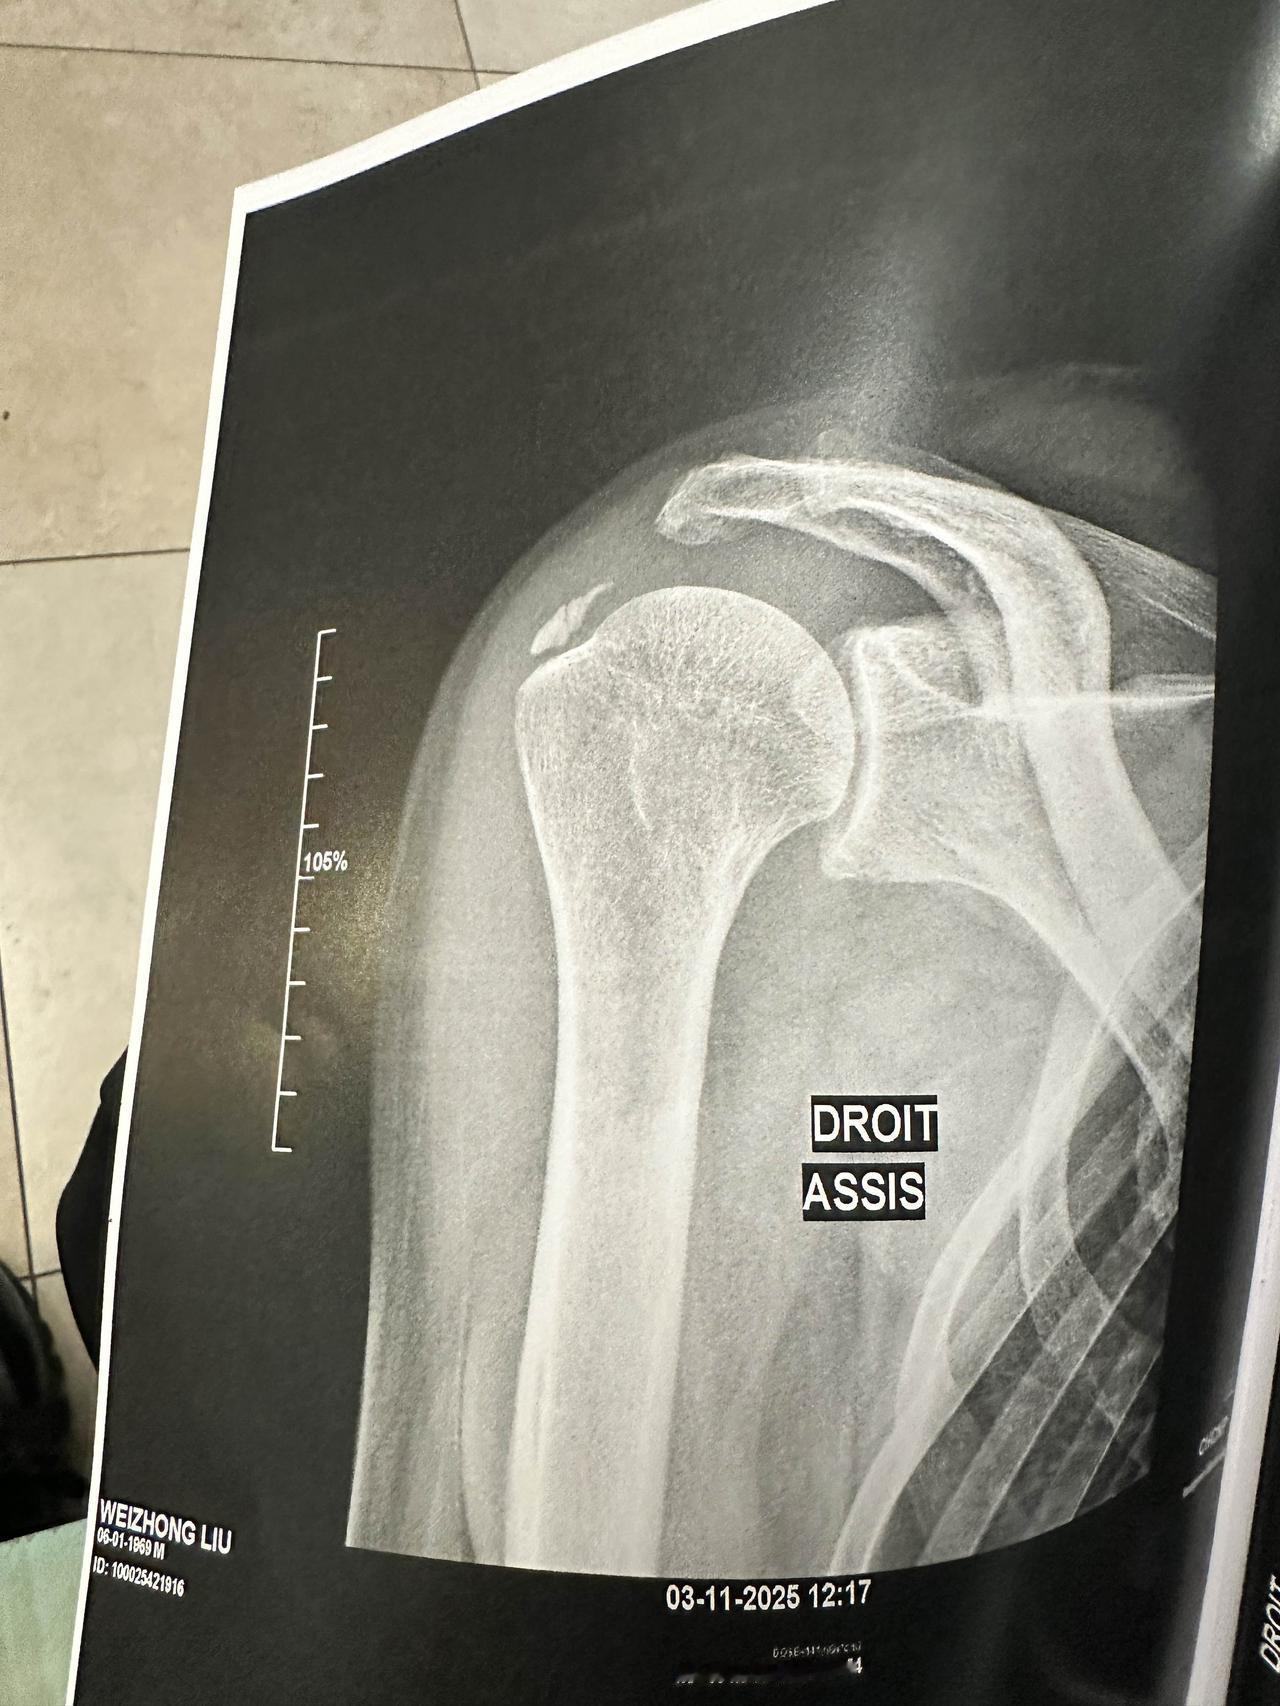

在法国看病的奇怪经历。 谢谢好多网友粉丝的关心,肩膀骨头没有大问题。 真的年纪大了什么都要注意,过马路一个趔趄肩膀都能摔的这么严重,第二天去了医院,拍了片子,没有骨折但可能有些错位。 我这次旅行是买了一年的旅游保险的,一年700块,任何小病和意外都在保险范围内,包括感冒发烧去医院治疗都报销的。 然后法国护士大夫基本是说法语的,我这次正好随身带了翻译机,比手机翻译确实方便多了。很多都是我在听同声传译,知道他们的意思。 不过最后我没他懂为什么没让我付款,治疗完大夫给我了两张诊断书就说我可以走了。我说我要付款吗,去哪里付款,他一愣,就叫了个黑人护士,带着我走了好几个楼,我估计是从急诊楼走到了门诊楼吧,进了个小屋里面有两个窗口,把我的单子递上去,大夫敲击了一下电脑,和旁边的人说了句什么,说今天不能交费,另一个人就说不用交费,让我可以走了。我很奇怪,也不好意思再问,一脸茫然的就走了。 这应该不是对外国人的福利吧?他们除了复印了我的护照没要其他东西,以后不会因为我没交费,说我逃避医疗费禁止给我签证和入境吧。